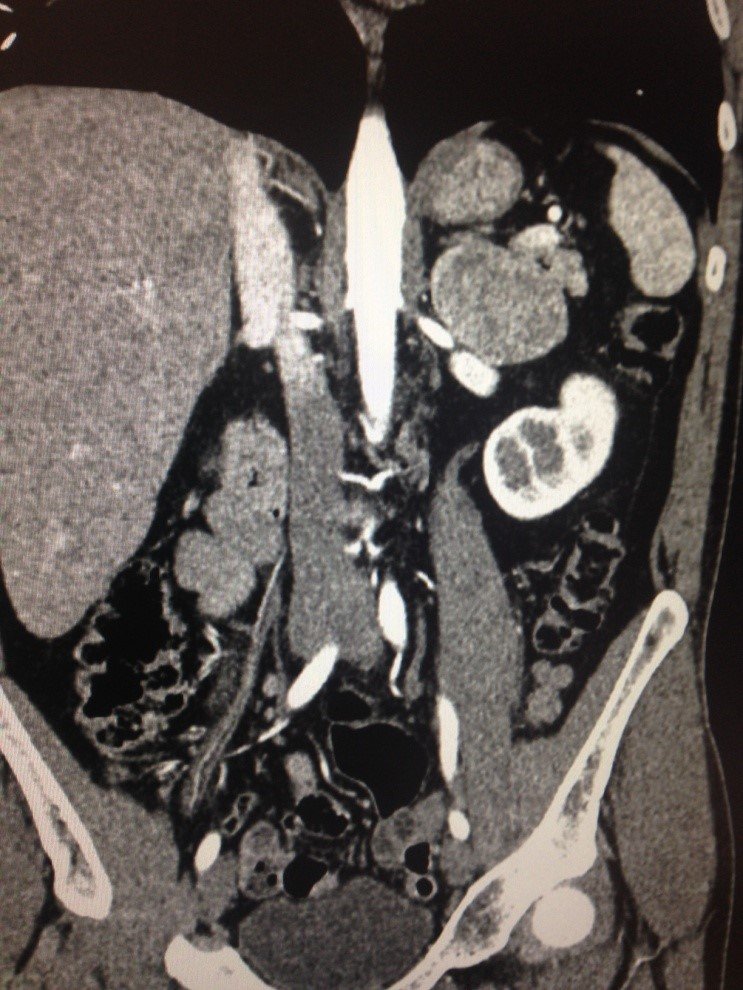

a

b

Şəkil 2. Soltərəfli Feoxromasitoma: a) abdominal Kompyuter tomoqrafiya, b) cərrahi əməliyyat görüntüsü.